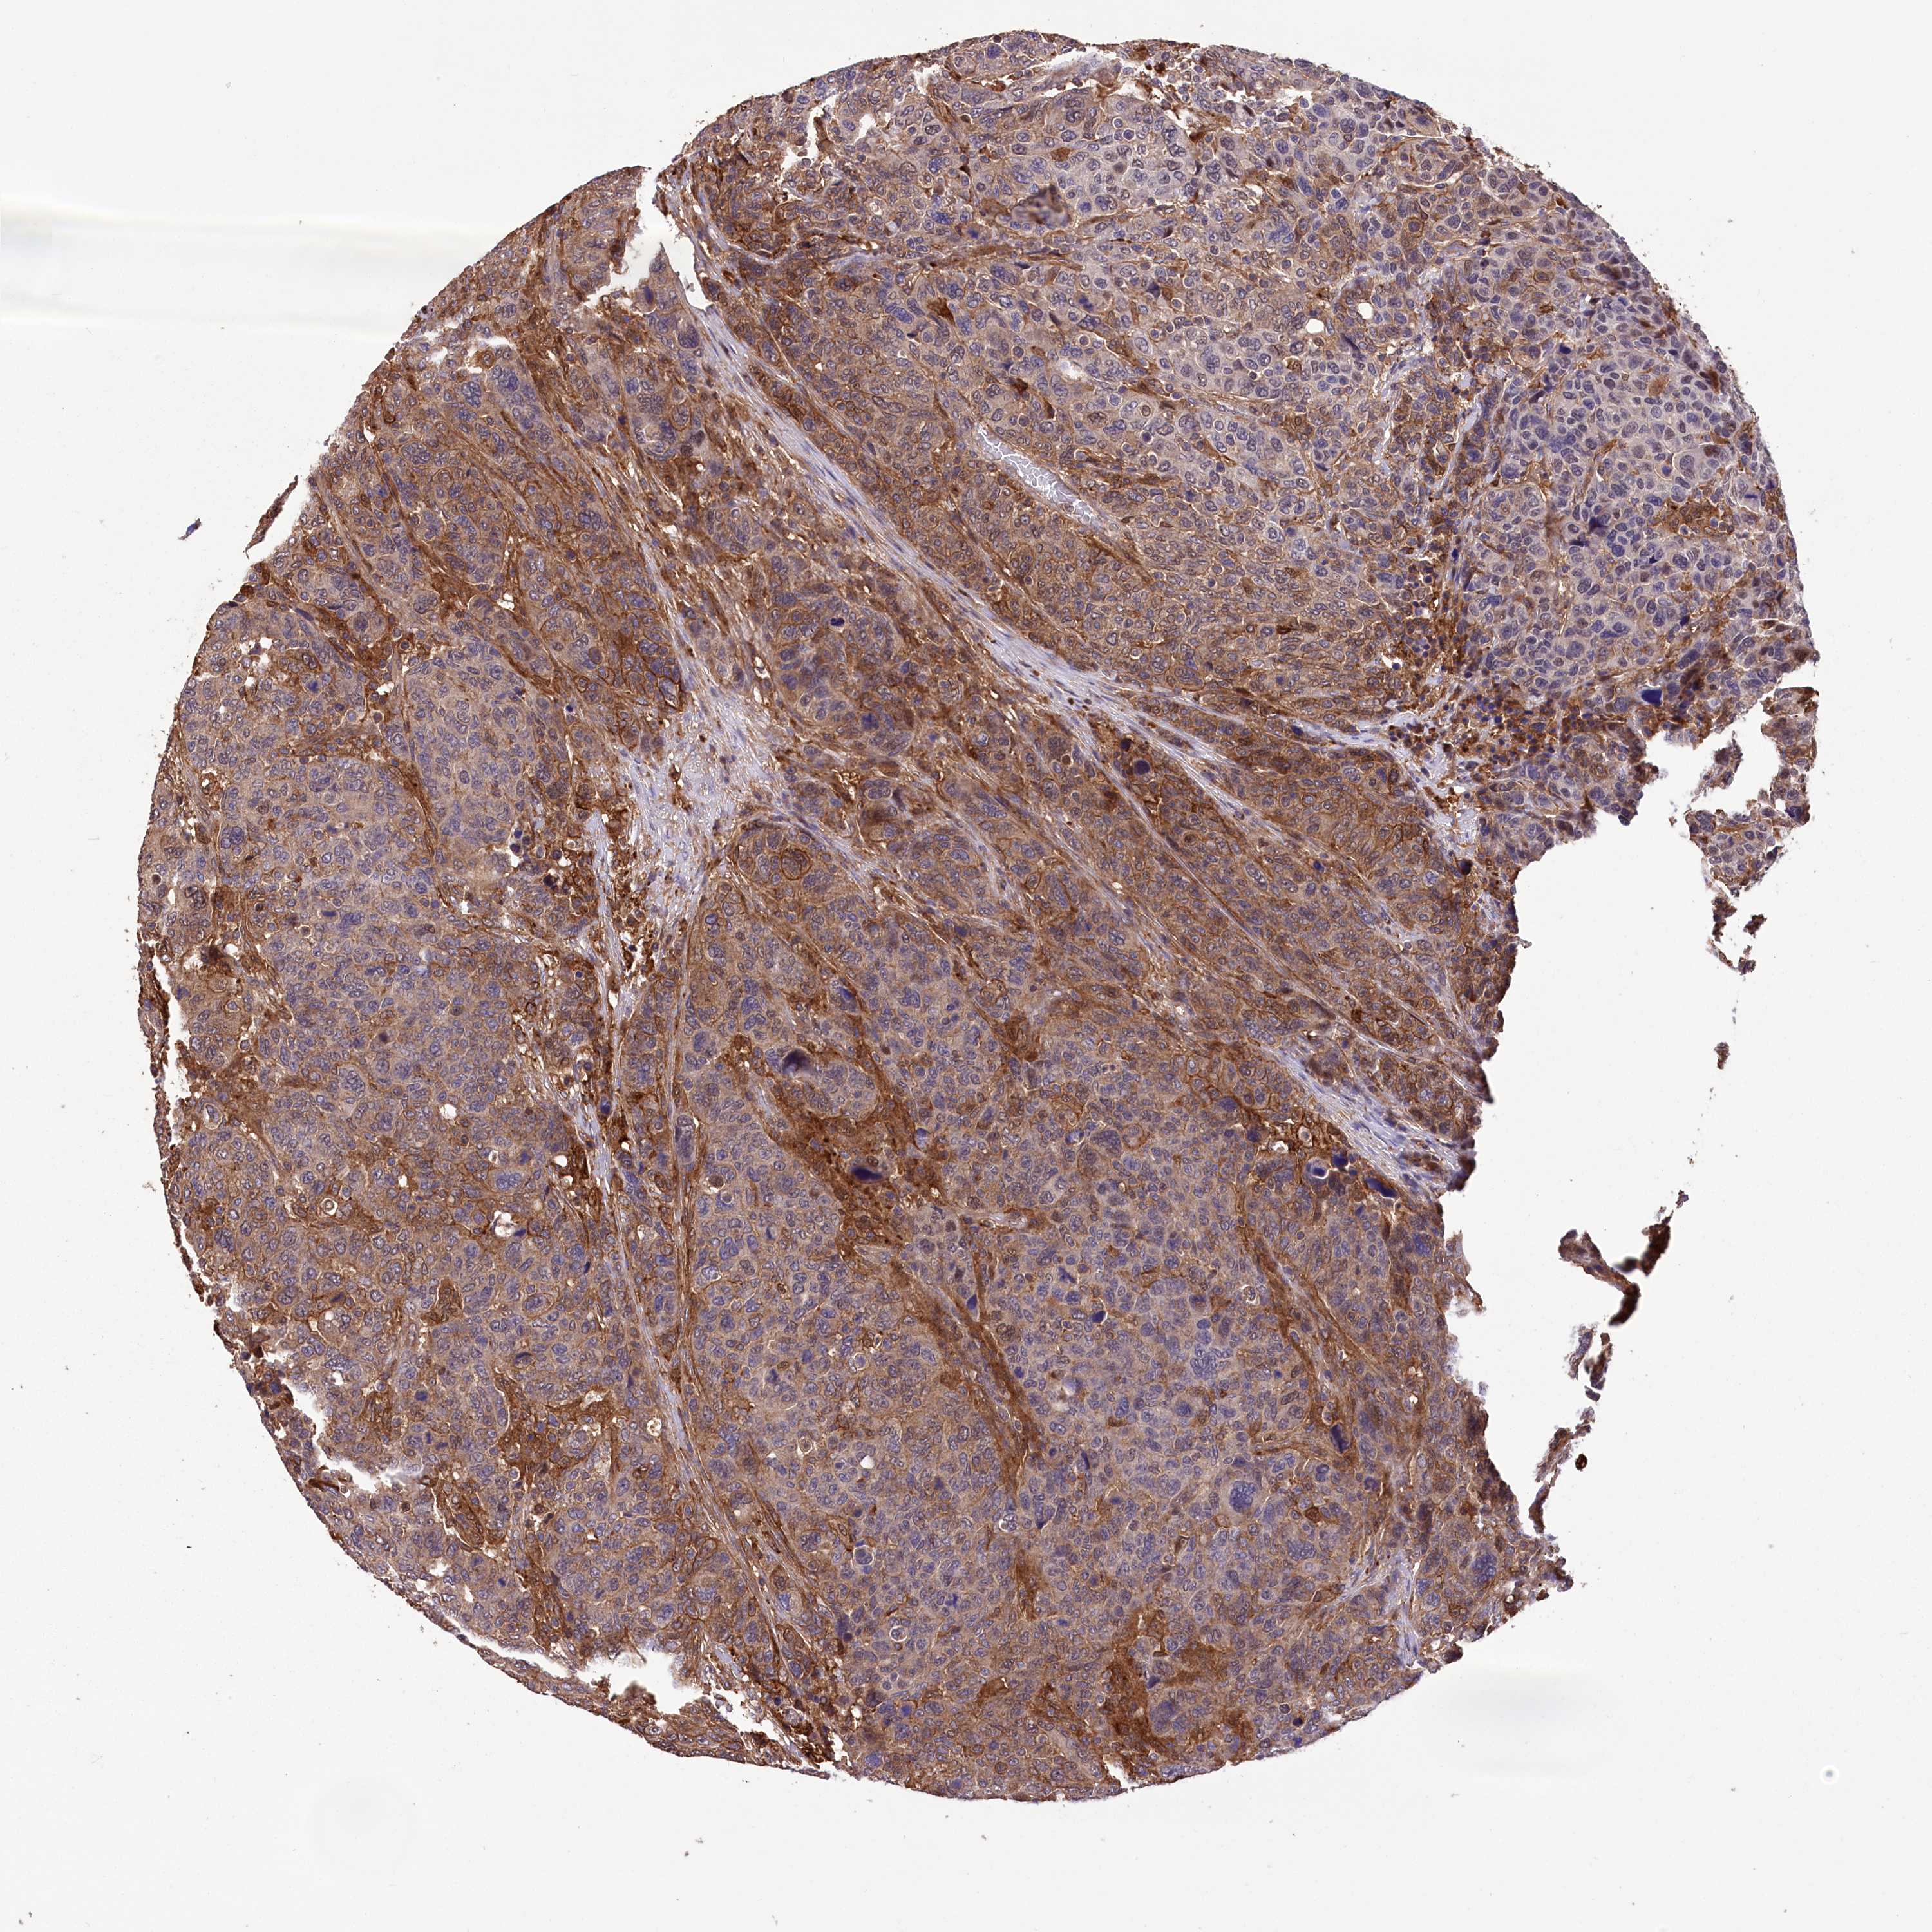

BRCA TCGA BRCA VALIDATION PROTEIN EXPRESSION